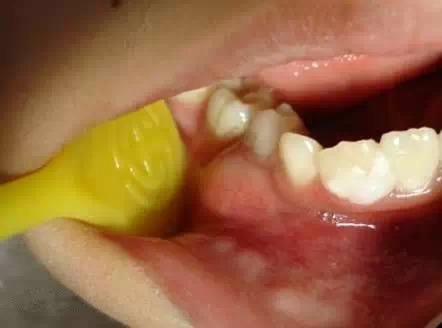

總結(jié)一下,1,在決定牙髓治療前一定要拍個X光片。有助于后續(xù)治療。

2,在可能的情況下,應(yīng)用局部麻醉,采用乳牙失活藥物。

3,國外的經(jīng)驗是,進(jìn)行持久完善的金屬預(yù)成冠保護(hù),效果好,防止微滲漏。可我們的國情很難做到。